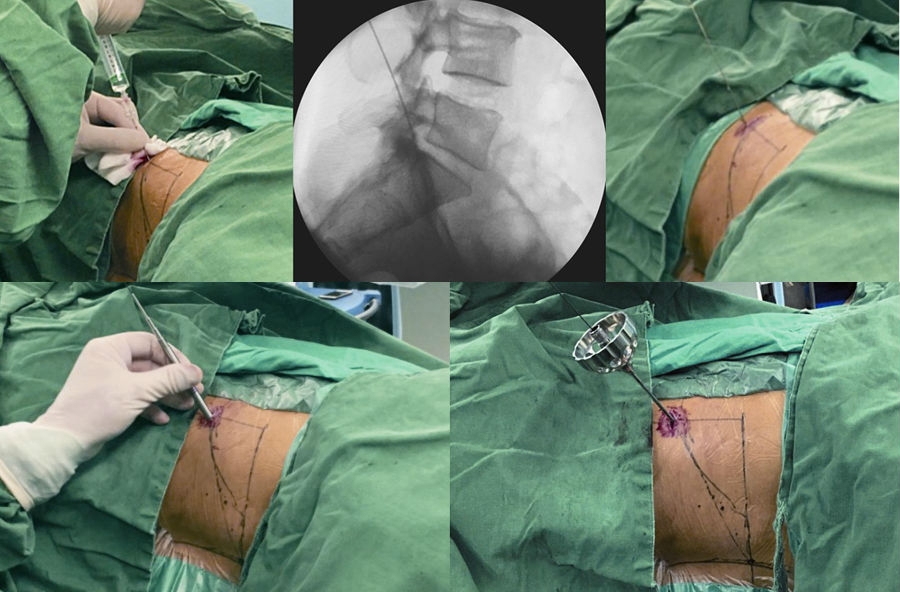

患者取侧卧位,患侧在上,健侧腰部垫高,以健侧髂骨刚离开床面为宜。(图3)

取后外侧入路,穿刺点L3~4为后正中线旁开 8~10cm,L4~5为 10~12cm,L5~S1为12~14cm,肥胖者各节段较普通患者多旁开1~2cm。(图 4)

使用1%利多卡因40ml进行逐层局部浸润麻醉,包括皮下组织、深筋膜和关节突关节。(图 5)

以L5~S1为例,根据髂嵴的高低,针尾向头侧倾斜约 40°~60°,外展角约 30°~50°,定位针在正位X线透视下刚好位于后背正中的棘突连线上,侧位X线透视下则紧贴上关节突腹侧,下缘位于下位椎体的后上缘。(图6)

做大约1cm皮肤切口,用导丝置换穿刺针,沿导丝用扩张器逐级扩大软组织。(图7、图8)

图3 定位板前后位X线片标定靶点和穿刺方向

A. 术前定位板标记体表位置;B.定位板X线射片投影图

图4 标记穿刺线

A. L5-S1椎间盘平面;B.棘突中线连线;C.穿刺假想体表投影

图5-图9 A:使用利多卡因进行局部分层麻醉(皮肤、皮下组织、筋膜、关节突周围);B:穿刺针X线片侧位投影图;C:穿刺到位后交换导丝;D:导丝引导下通过导杆、三级套管扩张肌肉及软组织;E:导丝引导下交换Tom针,定位上关节突